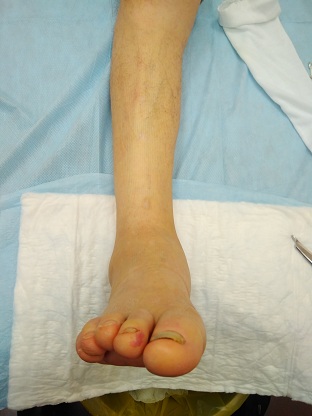

Диабетическая нейроостеоартропатия (ДНОАП) - одно из самых тяжелых осложнений сахарного диабета, требующее сотрудничества ряда специалистов, в том числе травматологов-ортопедов. Однако отсутствует единый подход в выборе тактики ортопедического лечения данной группы пациентов. С 2015 по 2018 гг. включительно наблюдались 35 пациентов с ДНОАП, которые получали консервативное или оперативное ортопедическое лечение. 11 пациентов получали консервативное ортопедическое лечение, хирургическое лечение получили 24 пациента. Всего выполнено 26 оперативных вмешательств. Выполнялось два типа хирургических вмешательств: 1) резекция выступающего фрагмента той или иной кости предплюсны - 12 операций; 2) реконструктивная операция, направленная на коррекцию грубой деформации среднего и/или заднего отдела стопы, - 14 операций. Наряду с общеклиническим обследованием всем пациентам проводились ортопедическое обследование, определение степени нарушения кровоснабжения. Дифференцированный подход к выбору метода ортопедического лечения представленной группы пациентов позволил восстановить опороспособность конечности, обеспечить стабильность в голеностопном суставе и суставах среднего отдела стопы, создать условия для заживления и предотвращения рецидива язвы. Полученный опыт позволил предложить показания для того или иного метода ортопедического лечения деформаций стоп при ДНОАП в зависимости от стадии патологического процесса, его локализации, степени выраженности деформации и клинического течения данной патологии.